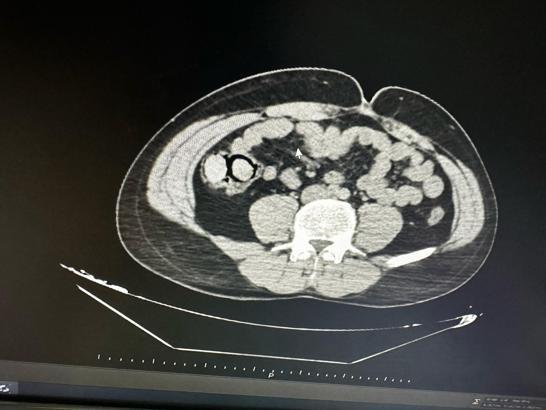

İl Emniyet Müdürlüğü Narkotik Suçlarla Mücadele Şube Müdürlüğü ekipleri tarafından gerçekleştirilen operasyonda, uyuşturucu ticareti yapmak üzere kente otobüsle geldiği bilgisine ulaşılan 2 şüpheli gözaltına alındı. Şüphelilerin hastanede yapılan muayenelerinde, midelerinde toplamda 10 parça halinde 113 gram metamfetamin maddesi ele geçirildi. Şüphelilerin midelerindeki uyuşturucu paketleri, hastanede yapılan işlemle çıkarıldı. Emniyetteki işlemlerinin ardından adliyeye sevk edilen şüpheliler, sevk edildikleri adliyede çıkarıldıkları mahkemece tutuklanarak cezaevine gönderildi.(DHA)